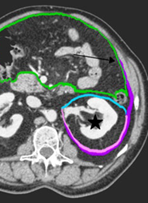

- Relatie van de tumor tot de mesocolische fascie (MCF+ofMCF-), waarbij een afstand ≤ 1 mm als positief wordt geclassificeerd (zie figuur 2).

Figuur 2a. Anatomie retroperitoneale ruimte (referentie: Coffin, 2015)

Groene lijn = peritoneum parietale en viscerale. Blauwe lijn = mesocolische fascie en anterieure renale fascie (samen 1 structuur op CT). Lateroconale fascie (paars) loopt door in de posterieure renale fascie (roze)

Figuur 2b Sagittale anatomie

Bij groei tot aan de mesocolische fascie (wat op CT niet te onderscheiden is van anterieure renale fascie) is er sprake van T3 stadium met een bedreigde marge; als de tumor door de mesocolische fascie groeit (en zich dus in een andere ruimte bevindt, is het T4b)